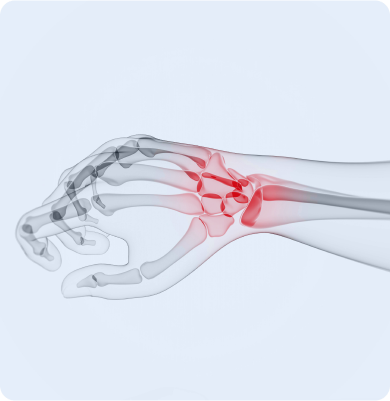

손목의 신경이 압박을 받아 발생하는 질환

반복적인 손목 움직임이나 과도한 압박, 장시간의 손목 사용 등이 주요 원인으로 특히 컴퓨터 작업이나 스마트폰 사용 등에서 발생할 수 있습니다.

손목의 새끼손가락 쪽 관절을 지지하는 삼각섬유연골복합체가 손상되거나 파열되는 질환

넘어지면서 손을 짚는 외상, 손목의 반복적인 회전 동작, 테니스나 골프처럼 손목을 많이 쓰는 스포츠 활동 등이 원인입니다.